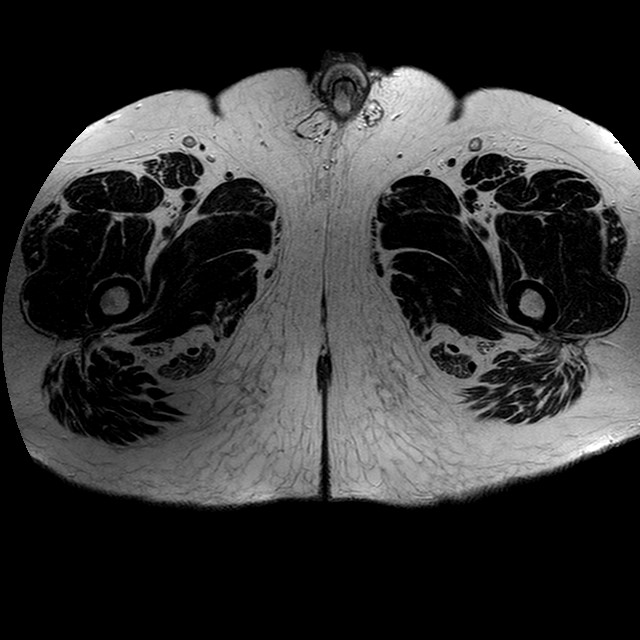

Esami: RMN BACINO

T2w TSE

Evidenti e simmetriche alterazioni osteofitosiche in regione coxo femorale con riduzione delle rime articolari. Degenerazione completa del cercine glenoideo. Non attuali segni di versamento articolare. Non segni di edema osseo che escludono attuale algodistrofia od osteonecrosi. Lieve e simmetrica riduzione del trofismo della muscolatura glutea.